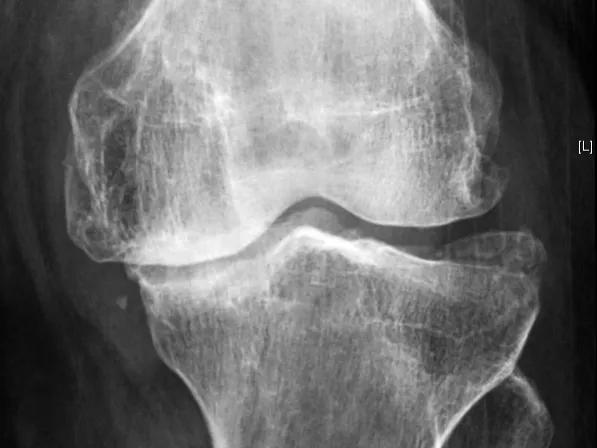

骨关节炎,也叫 退变性关节炎 或 老年性关节炎 ,其主要的病理基础就是 关节内软骨的磨损 ,随着年龄的增长、长期的使用以及外伤等因素,关节软骨表面不再光滑,磨损日渐加重,患者就会出现关节的疼痛、酸胀以及功能受限,严重的会导致残疾,它是老年人致残的主要原因之一。

但有一点要注意,那就是 骨关节炎患者的病情不能太重,适合早期和中期患者服用 ,如果经过检查患者的关节软骨磨损极其严重,关节间隙出现了明显的狭窄,关节周边已经有大量的骨赘形成,到了骨关节炎晚期的程度,就没有必要尝试了, 雄狮已经消失了,再补充养分也于事无补了 ,就是这个道理。